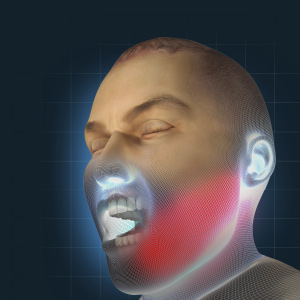

Oral Surgery Updates

Tuesday, October 1, 2024

This edition of the Compendium clinical eBook series features a continuing education (CE) article on the use of maxillomandibular advancement surgery for the treatment of obstructive sleep apnea in patients who are intolerant to continuous positive airway pressure (CPAP) or in whom CPAP or ...